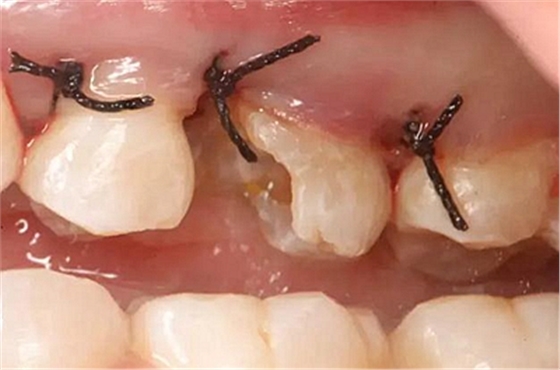

改良垂直褥式縫合關(guān)閉傷口,傷口無明顯滲血,高嵌體預(yù)備完畢后,硅橡膠取模,見邊緣清晰。灌注模型,模型上3MZ350XT分層堆塑高嵌體。

一周后拆除縫線,試戴高嵌體,試戴合適后雙固化粘結(jié)。調(diào)合,拋光。